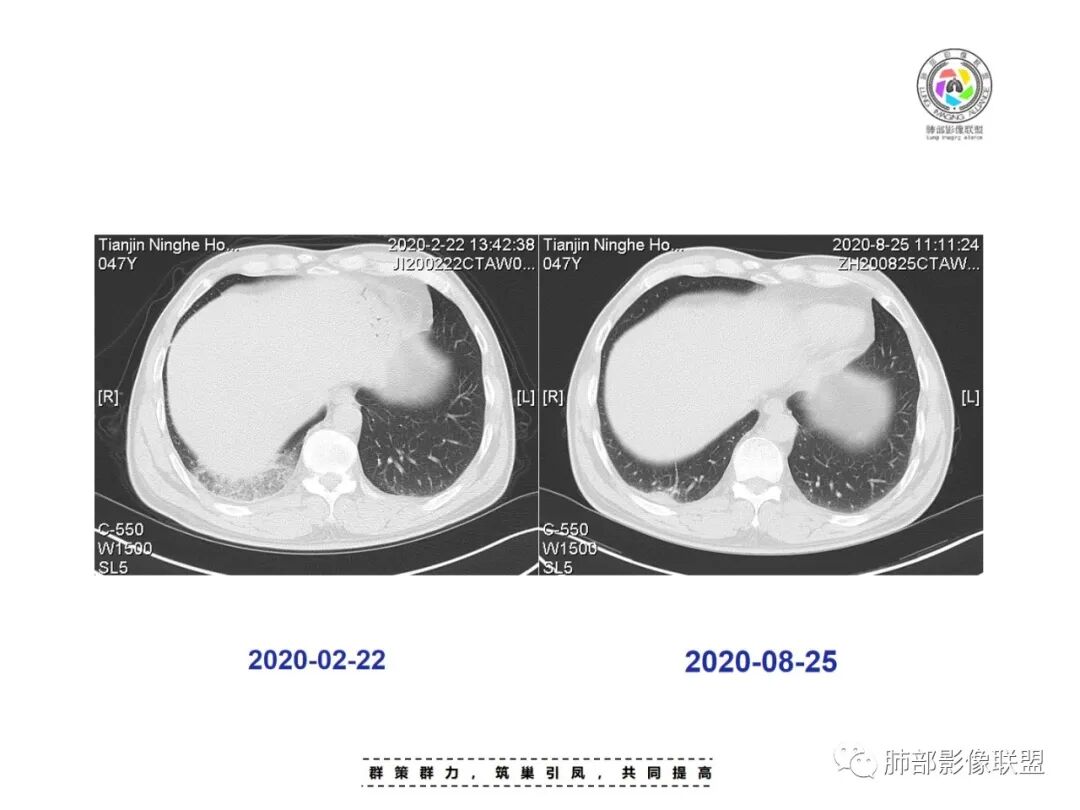

答案揭晓

肺动脉栓塞

急性肺栓塞发生后,因肺动脉血流阻断而引起供血动脉远端肺组织的坏死称为肺梗死。肺动脉分支一旦血流阻断,远端毛细血管网则因管壁缺氧而通透性增高,液体及红细胞随之渗出,肺泡腔内渗出物增加,必然会影响气体交换,随后肺梗死发生。既往有研究表明,肺外周楔形阴影可以认为是肺梗死的征象,是唯一与肺栓塞显著相关的肺实性异常,该征象在肺栓塞患者中的发生率为25%。